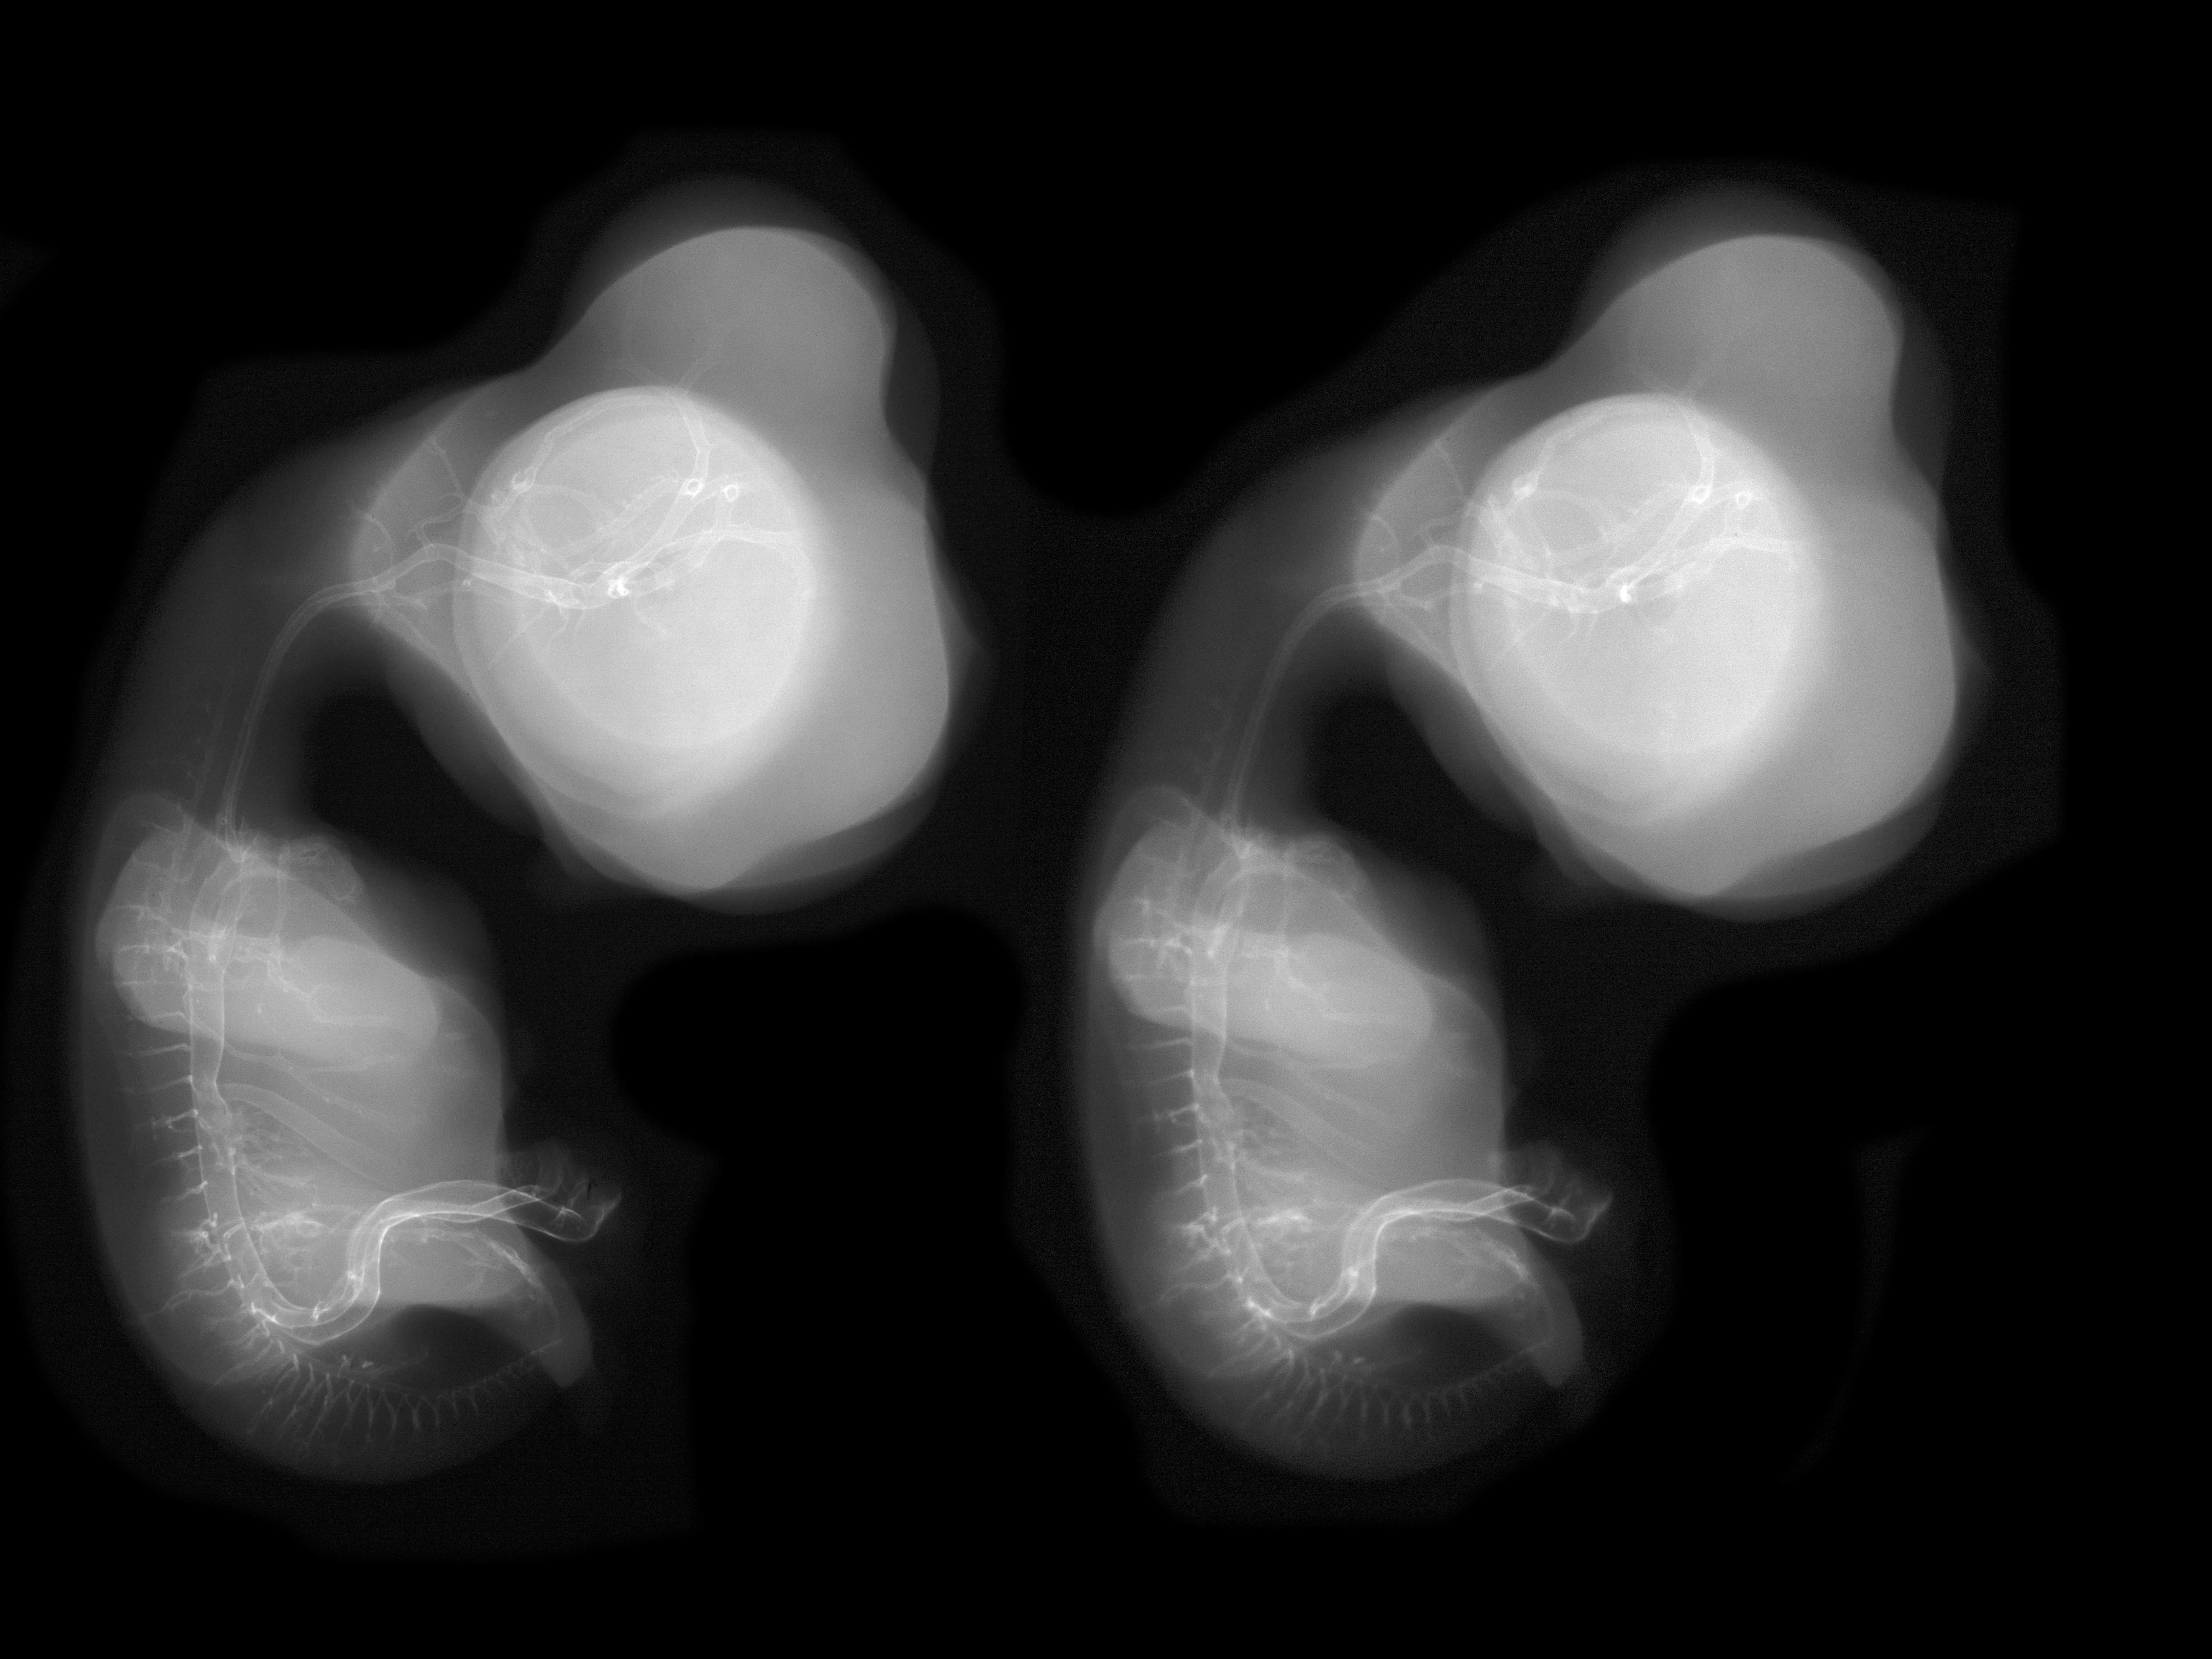

Chick Embryo Microangiography

Hamburger-Hamilton (HH) Stage 30 (approx. 6.5 days)

Stereo X-Ray Micrographs